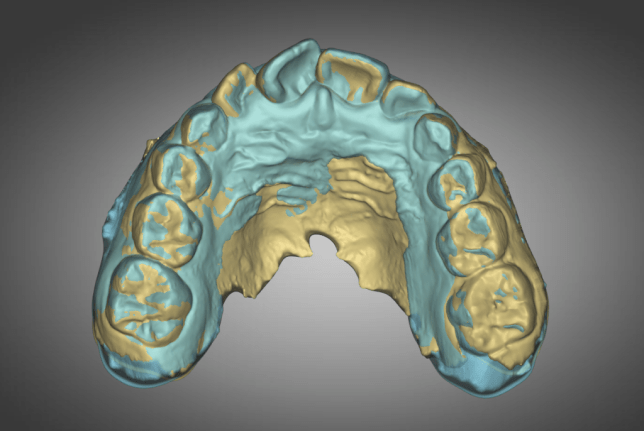

1st Review – 2023-03-01

- YELLOW = Initial 2022-10-29

- BLUE = 1st Review 2023-03-01

Compliance was not good in the first quarter. Not much expansion seen on buccal side

2nd Review – 2023-05-30

- BLUE = 2nd Review2023-05-30

Second quarter has signs of better compliance with evidences of expansion bilaterally as seen by the blue on the buccal(cheek) sides of the posterior teeth.